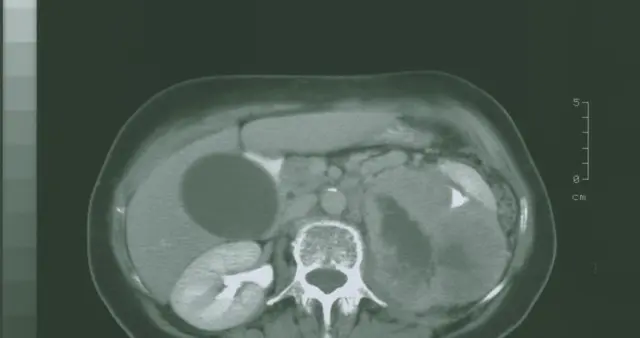

忽视肚子变大可能拖成肝腹水!肝病患者必看

肝硬化真的可怕吗?源头治肝一个疗程,肝弹值从22.5降至10.3!